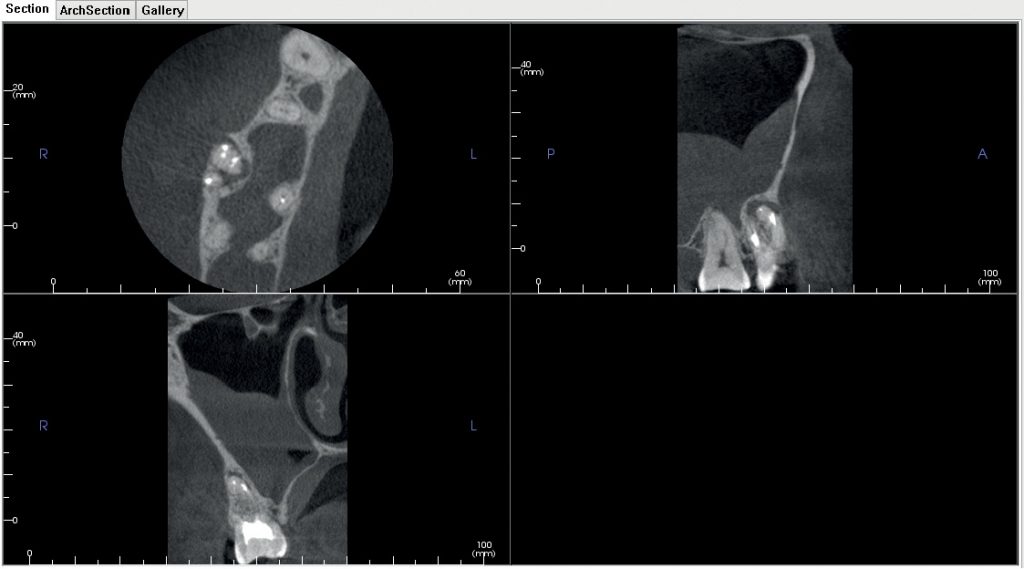

Streszczenie: Leczenie endodontyczne pierwszych górnych zębów trzonowych, ze względu na ich skomplikowaną anatomię i błędy proceduralne, może zakończyć się niepowodzeniem. Brak możliwości przeprowadzenia powtórnego leczenia kanałowego w przypadku zmian zapalnych w tkankach okołowierzchołkowych skłania do wprowadzenia metod chirurgicznych. Korzenie policzkowe bliższe posiadają zróżnicowaną konfigurację systemu kanałowego, co może stanowić wyzwanie dla operatora. Dodatkowa diagnostyka w postaci komputerowej stożkowej tomografii wolumetrycznej oraz zastosowanie odpowiedniego powiększenia podczas zabiegu mogą przyczynić się do osiągnięcia sukcesu leczenia. W artykule opisano przypadek resekcji wierzchołka korzenia policzkowego bliższego zęba 16, ze wstecznym usunięciem złamanego instrumentu oraz z retrowypełnieniem kanałów MB1 i MB2. 9-miesięczna obserwacja wykazała pozytywny wynik leczenia.

Summary: Endodontic treatment of the upper first molars may fail, due to their complicated anatomy and procedural errors. Impossibility of a retreatment, in the case of inflammatory changes in the [...]